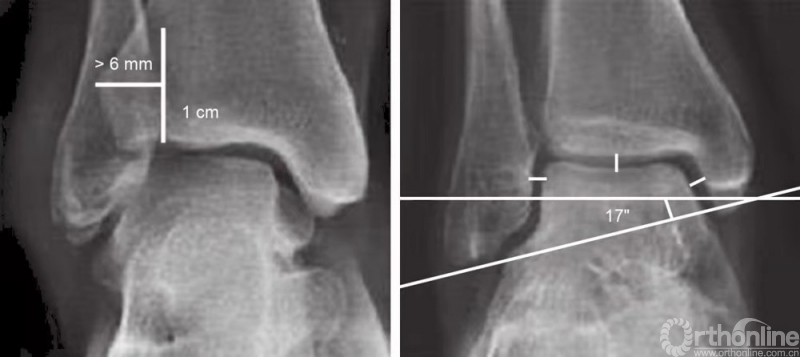

为识别骨折线、关节半脱位以及可能的下胫腓联合损伤,须具备高质量的踝关节前后位片、踝穴位片和侧位片。在踝关节的前后位片中,内侧、外侧和上方的关节间隙应该等大。内侧的关节间隙实际应小于4mm,如果大于4mm,则表明外侧距骨半脱位。腓骨远端的内侧面应延伸至距骨的关节边缘。距骨小腿角间接测量了腓骨的长度,度数应为83±4度。正常情况下,下胫腓的关节间隙为4mm,如果大于6mm,则表明下胫腓联合断裂。在前后位片中,腓骨远端与胫骨远端会出现约6mm的重合影(高出关节线1cm)(图1)。

图1 正常踝关节前后位及踝穴位